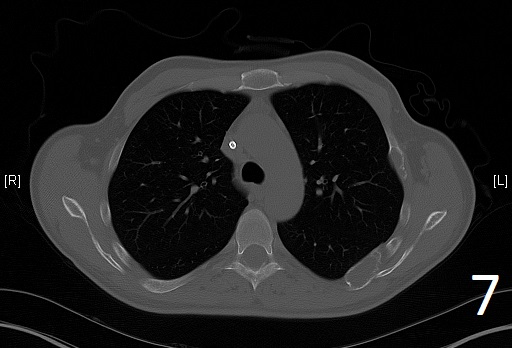

Fig. 6

Fig. 7

Fig. 6-7. Axial CT reconstruction of the chest showing lytic and expansile lesion of the left scapula and ribs (polyostotic fibrous dysplasia).